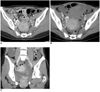

Imaging findings are presented for 37-year-old woman with interstitial pregnancy.

A. Initial contrast enhanced axial CT image shows strong enhancing ring-like mass (arrow) that represents gestational sac without hemoperitoneum. Mass abuts uterine fundus in right pelvis.

B. Follow-up CT image obtained after four days shows amorphous hematoma (arrowheads) with massive hemoperitoneum caused by ruptured interstitial pregnancy. Previous strong enhancing ring-like mass in right pelvis is now seen as heterogeneous enhancing mass (arrow) after rupture of interstitial pregnancy.

C. Coronal multiplanar reconstruction CT image shows heterogeneous enhancing mass (arrow) that abuts uterine fundus (arrowheads), suggestive of interstitial pregnancy. Note that there is hypodense line between mass and uterine fundus. CT image demonstrates hematoma around uterus and hemoperitoneum.